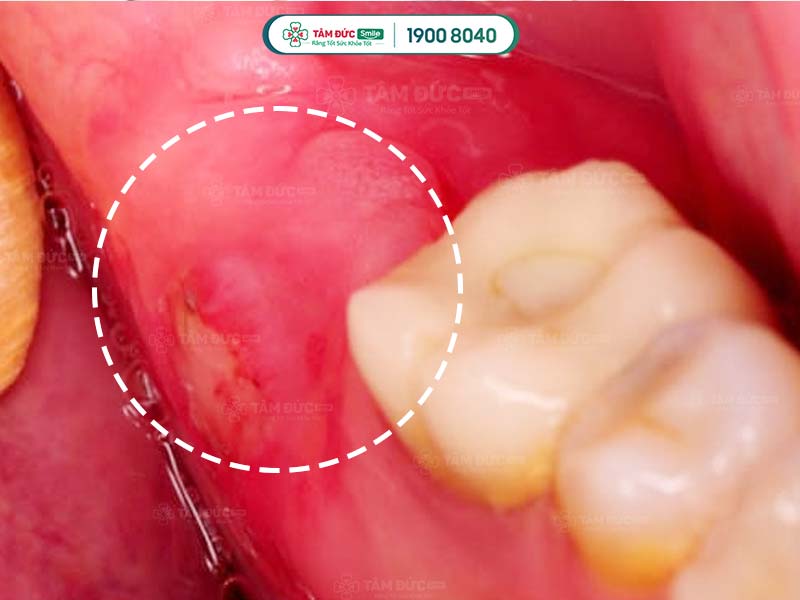

Viêm sưng nướu răng trong cùng

Bên cạnh đó, viêm lợi trùm cũng là nguyên nhân dẫn tới sưng nướu răng. Bị sưng nướu răng trong cùng hàm dưới do viêm lợi trùm thường đi kèm với hiện tượng chảy mủ và hôi miệng.